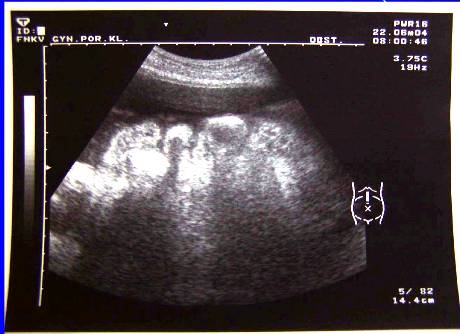

3.Duplicita (pac.M.B.-tu markery, laparotomia, radikální operace pro Ca ovarii, peroperační biopsie)

Duplicita (pac.M.B.-tu markery, laparotomia, radikální operace pro Ca ovarii, peroperační biopsie)

Duplicita(pac.M.B.-tu markery, laparotomia, radikální operace pro Ca ovarii, peroperační biopsie)

Duplicita (pac.M.B -laparotomia, radikální operace pro Ca ovarii, peroperační biopsie)